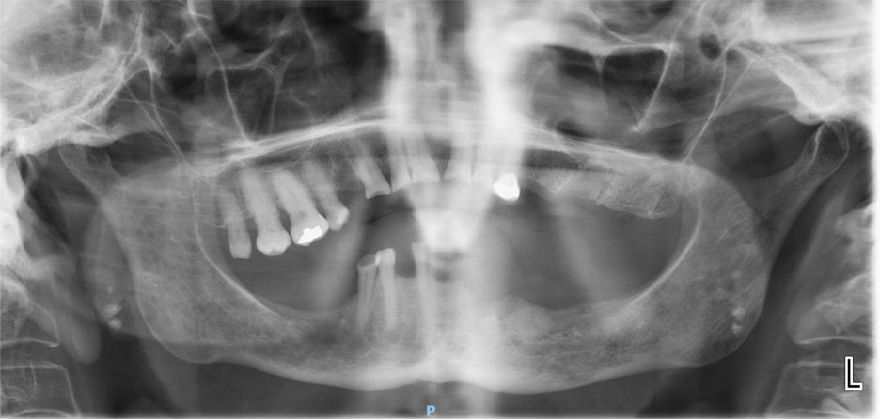

The patient is a 54-year-old female with a history of Stage 4 metastatic breast cancer treated with chemotherapy and radiation. She was treated with zoledronic acid (Zometa) beginning in June 2020. The patient was referred to Denver Health OMS by her dentist regarding non-healing extraction sites and additional extractions. In mid-2022, about three months prior to the referral, her dentist had extracted teeth #29 to #31. On examination, the patient had Stage 2 MRONJ along with painful, periodontally compromised, non-restorable teeth. Following a consultation with oncology and infectious disease, the decision was made to debride the MRONJ area and remove the remaining teeth in the operating room with the patient on long-term antibiotic coverage. Within two to three months, MRONJ had recurred and in April 2023, the patient subsequently underwent a right posterior mandibular resection with an antibiotic spacer placed in the resected area.